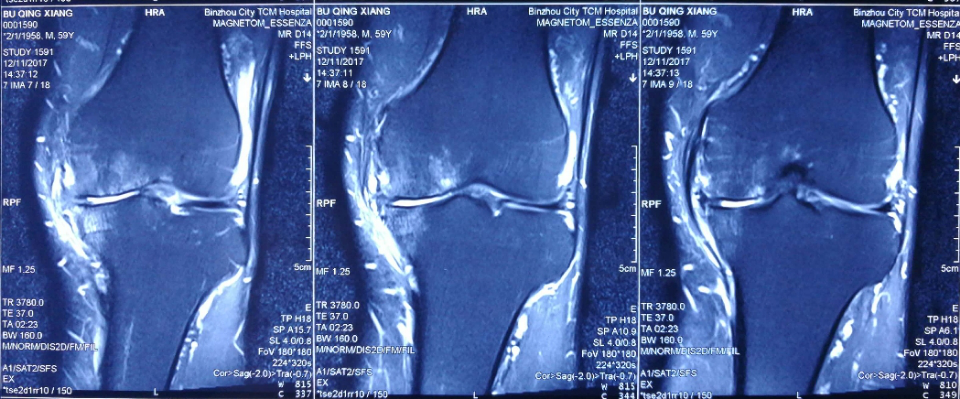

术前MRI显示:患者左膝内侧股骨髁及胫骨平台骨髓水肿及半月板损伤